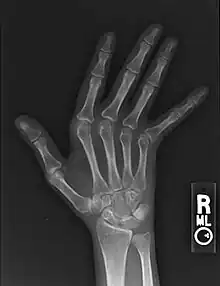

Jaccoud arthropathy seen on a hand x-ray. As opposed to arthropathy due to rheumatoid arthritis, there are no erosions.

Plain hand radiographs typically show marked ulnar subluxation and deviation at the metacarpophalangeal joints. Absence of erosions is a notable feature, although occasionally "hook" erosions may be observed, which are similar to those seen in SLE and ankylosing spondylitis. Evidence of muscle (soft tissue) atrophy also may be present.